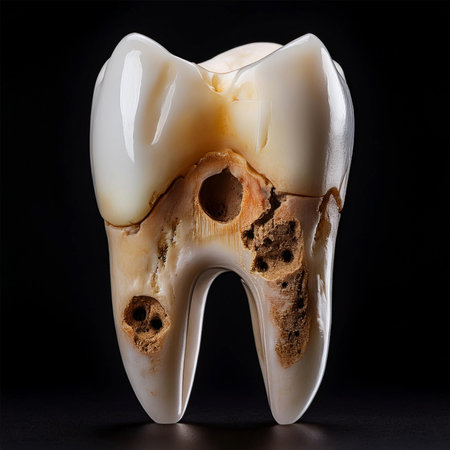

Tooth decay on black background. Macro shot of a decayed teeth till root after extraction of dentist. Real tooth anatomy due lack of care. Top view of caries teeth texture on black paper. Dental care.

The image depicts a tooth with severe tooth decay, characterized by visible cavities and brown discoloration.

Tooth decay on black background. Macro shot of a decayed teeth till root after extraction of dentist. Real tooth anatomy due lack of care. Top view of caries teeth texture on black paper. Dental care.

Tooth decay on black background. Macro shot of a decayed teeth till root after extraction of dentist. Real tooth anatomy due lack of care. Top view of caries teeth texture on black paper. Dental care.

This detailed image shows a cross-section of a tooth's anatomy, highlighting areas affected by tooth decay and cavities. It is visually informative and crucial for understanding dental issues.

This detailed image shows a cross-section of a tooth's anatomy, highlighting areas affected by tooth decay and cavities. It is visually informative and crucial for understanding dental issues.

The image depicts a tooth with severe tooth decay, characterized by visible cavities and brown discoloration.